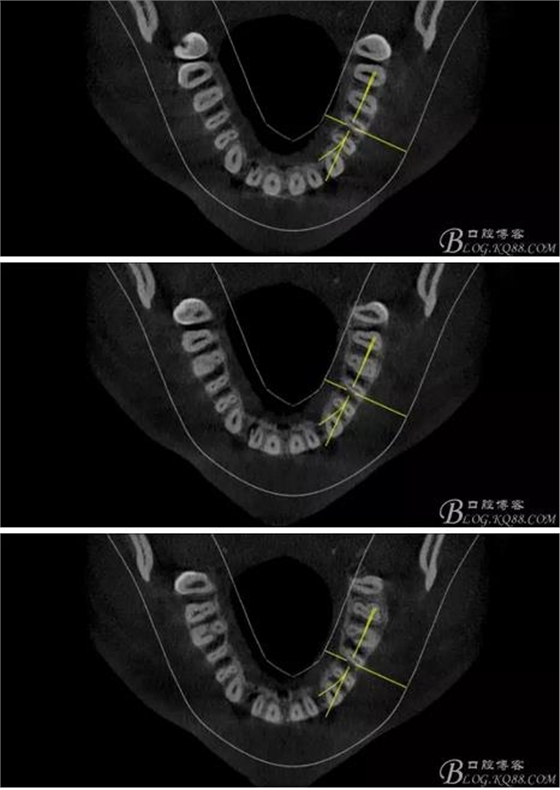

(1)檢查:12唇側(cè)牙齦可見竇道,牙體顏色較鄰牙暗,無光澤,形態(tài)完整無缺損,唇側(cè)及近遠(yuǎn)中向未提及牙周袋。腭側(cè)齦緣輕度紅腫,舌側(cè)窩可探及裂溝,可見浸墨狀痕跡,沿裂溝舌側(cè)探診牙周袋深大于11mm,除患牙外全口牙周狀況良好,為探及牙周袋,牙齦色粉紅。邊緣菲薄,質(zhì)地堅韌。12冷熱診無反應(yīng),叩診(+-),無明顯松動,無咬合創(chuàng)傷。12根尖x線片示,根管中三分之一中可見一斜向線樣透射影像根尖區(qū)及遠(yuǎn)中根三分之一可見低密度透射暗影,錐形束CT示12根尖區(qū)唇腭向骨吸收已穿通,根面溝達(dá)根中三分之一卷曲分出另一牙根,再未見其他明顯的根管系統(tǒng)。